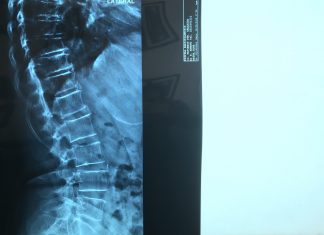

Οστεοπορωτικά σπονδυλικά κατάγματα σπονδυλικής στήλης

Τι θεωρείται οστεοπορωτικό κάταγμα σπονδυλικής στήλης;

Είναι η απώλεια του ύψους του σπονδύλου, χωρίς απαραίτητα να έχει προηγηθεί κάκωση ή μετά από μικρής βίας κάκωση....